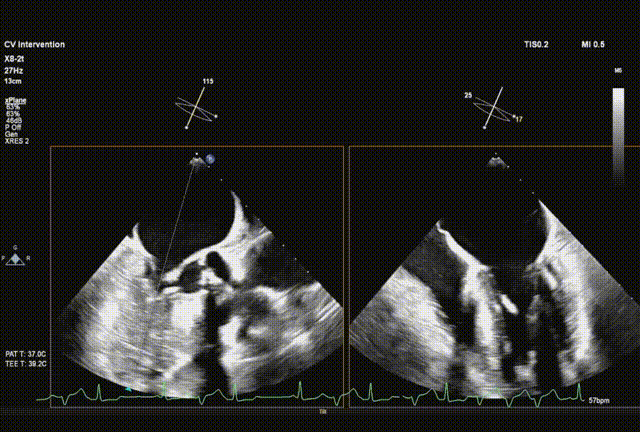

超声从左至右,最后无冠窦侧评估深度合适

起搏下完全释放瓣膜

左右旋转系统并前送,观察无瓣膜移动,回撤导丝后再撤出系统

术后超声评估,未见瓣周漏,平均跨瓣压15 mmHg,血流速度197 cm/s